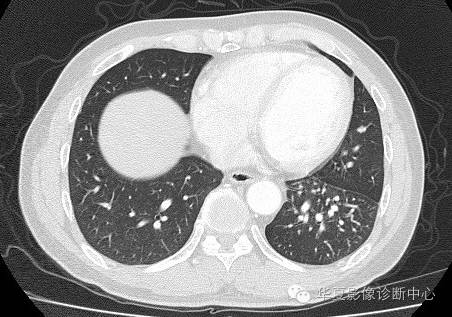

| 影像表现及分析: | 影像表现:定位左下叶;左下叶体积缩小,整体密度增高,支气管分布正常,其内见血管增多,但是走形正常,未见杂乱、迂曲的血管影;血管连向肺门下方软组织密度结节灶,结节与主动脉分界不清,增强后,见降主动脉发出异常粗大血管供血整个左下叶,左下肺动脉细小。 |

异常体动脉供应正常下肺基底段完整含义为起源于降主动脉的异常动脉供应下肺基底段,而基底段支气管树和肺实质正常,同时基底段肺动脉缺如或狭窄【大部分缺如(完全型),部分狭窄(不完全型)】;95%以上累及左下肺,因此也称为异常体动脉供应正常左下肺基底段。 病因尚未明确,可能是胚胎发育时期供应肺芽的背主动脉原始小分支退化不全,与肺实质形成异常连接,并影响肺动脉与肺血管床连接而导致此部位肺动脉发育不良,而支气管、肺组织的发育未受影响。本病的病理生理基础为左向左的分流,体动脉供应的肺组织充血,体循环的高压可增加肺血管床的压力和左心负荷,同时也增加肺循环量和压力而增加右心负荷,导致各种临床症群。本病可无临床症状,部分患者可有咯血、呼吸道感染、呼吸困难、充血性心力衰竭。 影像表现:左肺下叶体积缩小,整体密度稍增高,支气管树走形、分布正常,血管增多、稍增粗;增强后显示左下肺动脉幼小,甚至不发育;下叶由主动脉发出的粗大血管供血。 |